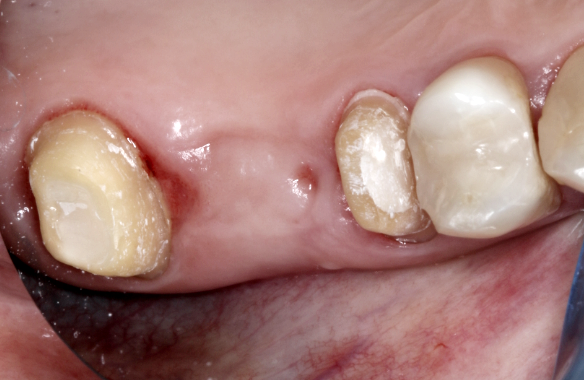

A foghiányt közrefogó fogakat előkészítettük (lecsiszoltuk) a hídpótláshoz.

hídpótlás előtt